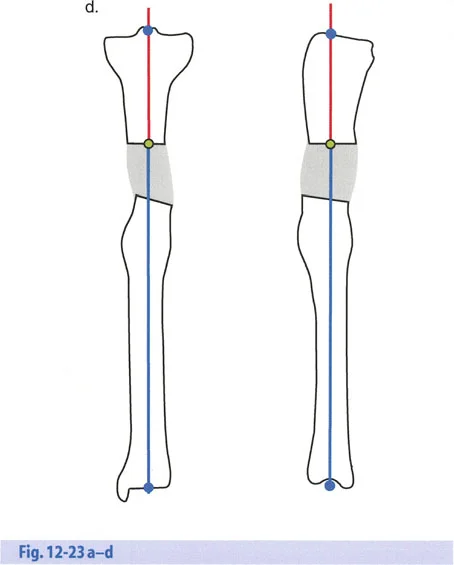

فهم المحور الميكانيكي للجسم

يعتمد جسم الإنسان على محاذاة دقيقة للمفاصل والعظام ليعمل بكفاءة. "المحور الميكانيكي" هو خط وهمي يمتد من مركز مفصل الورك إلى مركز مفصل الكاحل، ويمر عبر مركز مفصل الركبة. عند وجود تشوه، ينحرف هذا المحور، مما يضع ضغطًا غير طبيعي على المفاصل ويؤدي إلى الألم، وتآكل المفاصل المبكر (الخشونة)، وصعوبة في الحركة.

- الأشعة السينية الطويلة للطرفين (Long-leg Standing X-rays): هذه الأشعة ضرورية لتقييم المحور الميكانيكي للطرف بالكامل أثناء الوقوف. تسمح بتحديد مركز دوران الانحراف (CORA) بدقة، وهو النقطة التي يجب أن تتمحور حولها عملية التصحيح.

القياسات الهندسية:

- باستخدام صور الأشعة السينية الطويلة، يقوم الأستاذ الدكتور محمد هطيف بإجراء قياسات هندسية دقيقة لتحديد الزوايا غير الطبيعية (مثل mLDFA و MPTA)، ومقدار القصر، ودرجة الدوران، وأي انحرافات في المحور الميكانيكي. هذه القياسات هي الأساس لتخطيط الجراحة بدقة متناهية.